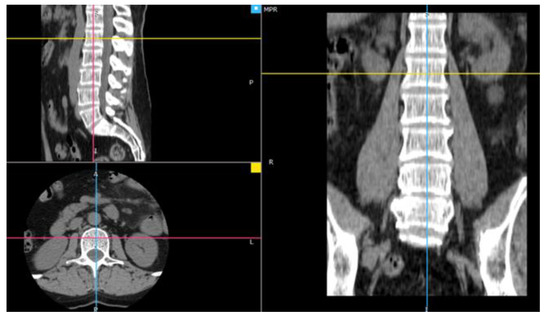

2.1. Material